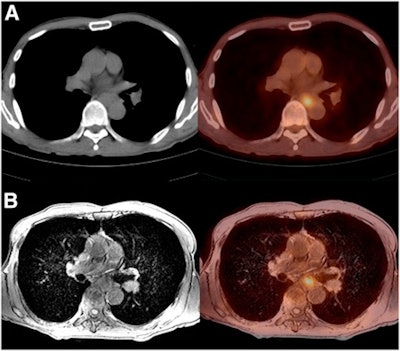

Chest scans were performed using a 64-detector-row CT scanner (Discovery CT750 HD, GE Healthcare), while FDG-PET/CT imaging was conducted on a combined PET/CT system (Gemini, Philips Healthcare) with a full-ring PET scanner and dual-slice helical CT.

FDG-PET/MR images were acquired on a sequential-acquisition PET/MRI system (Ingenuity TF, Philips), which combines a time-of-flight PET scanner and 3-tesla MRI. EUS exams were done with a radial echoendoscope (GF-UM-2000 or UM-DP20-25R, Olympus). All patients allowed passage of the echoendoscope through the esophagus, stomach, and duodenum.

Two chest radiologists and two nuclear medicine physicians retrospectively reviewed the images and assigned tumor and lymph-node stages in consensus. PET/CT scans were excluded from the tumor-staging analysis, but all four modalities were utilized for nodal staging.